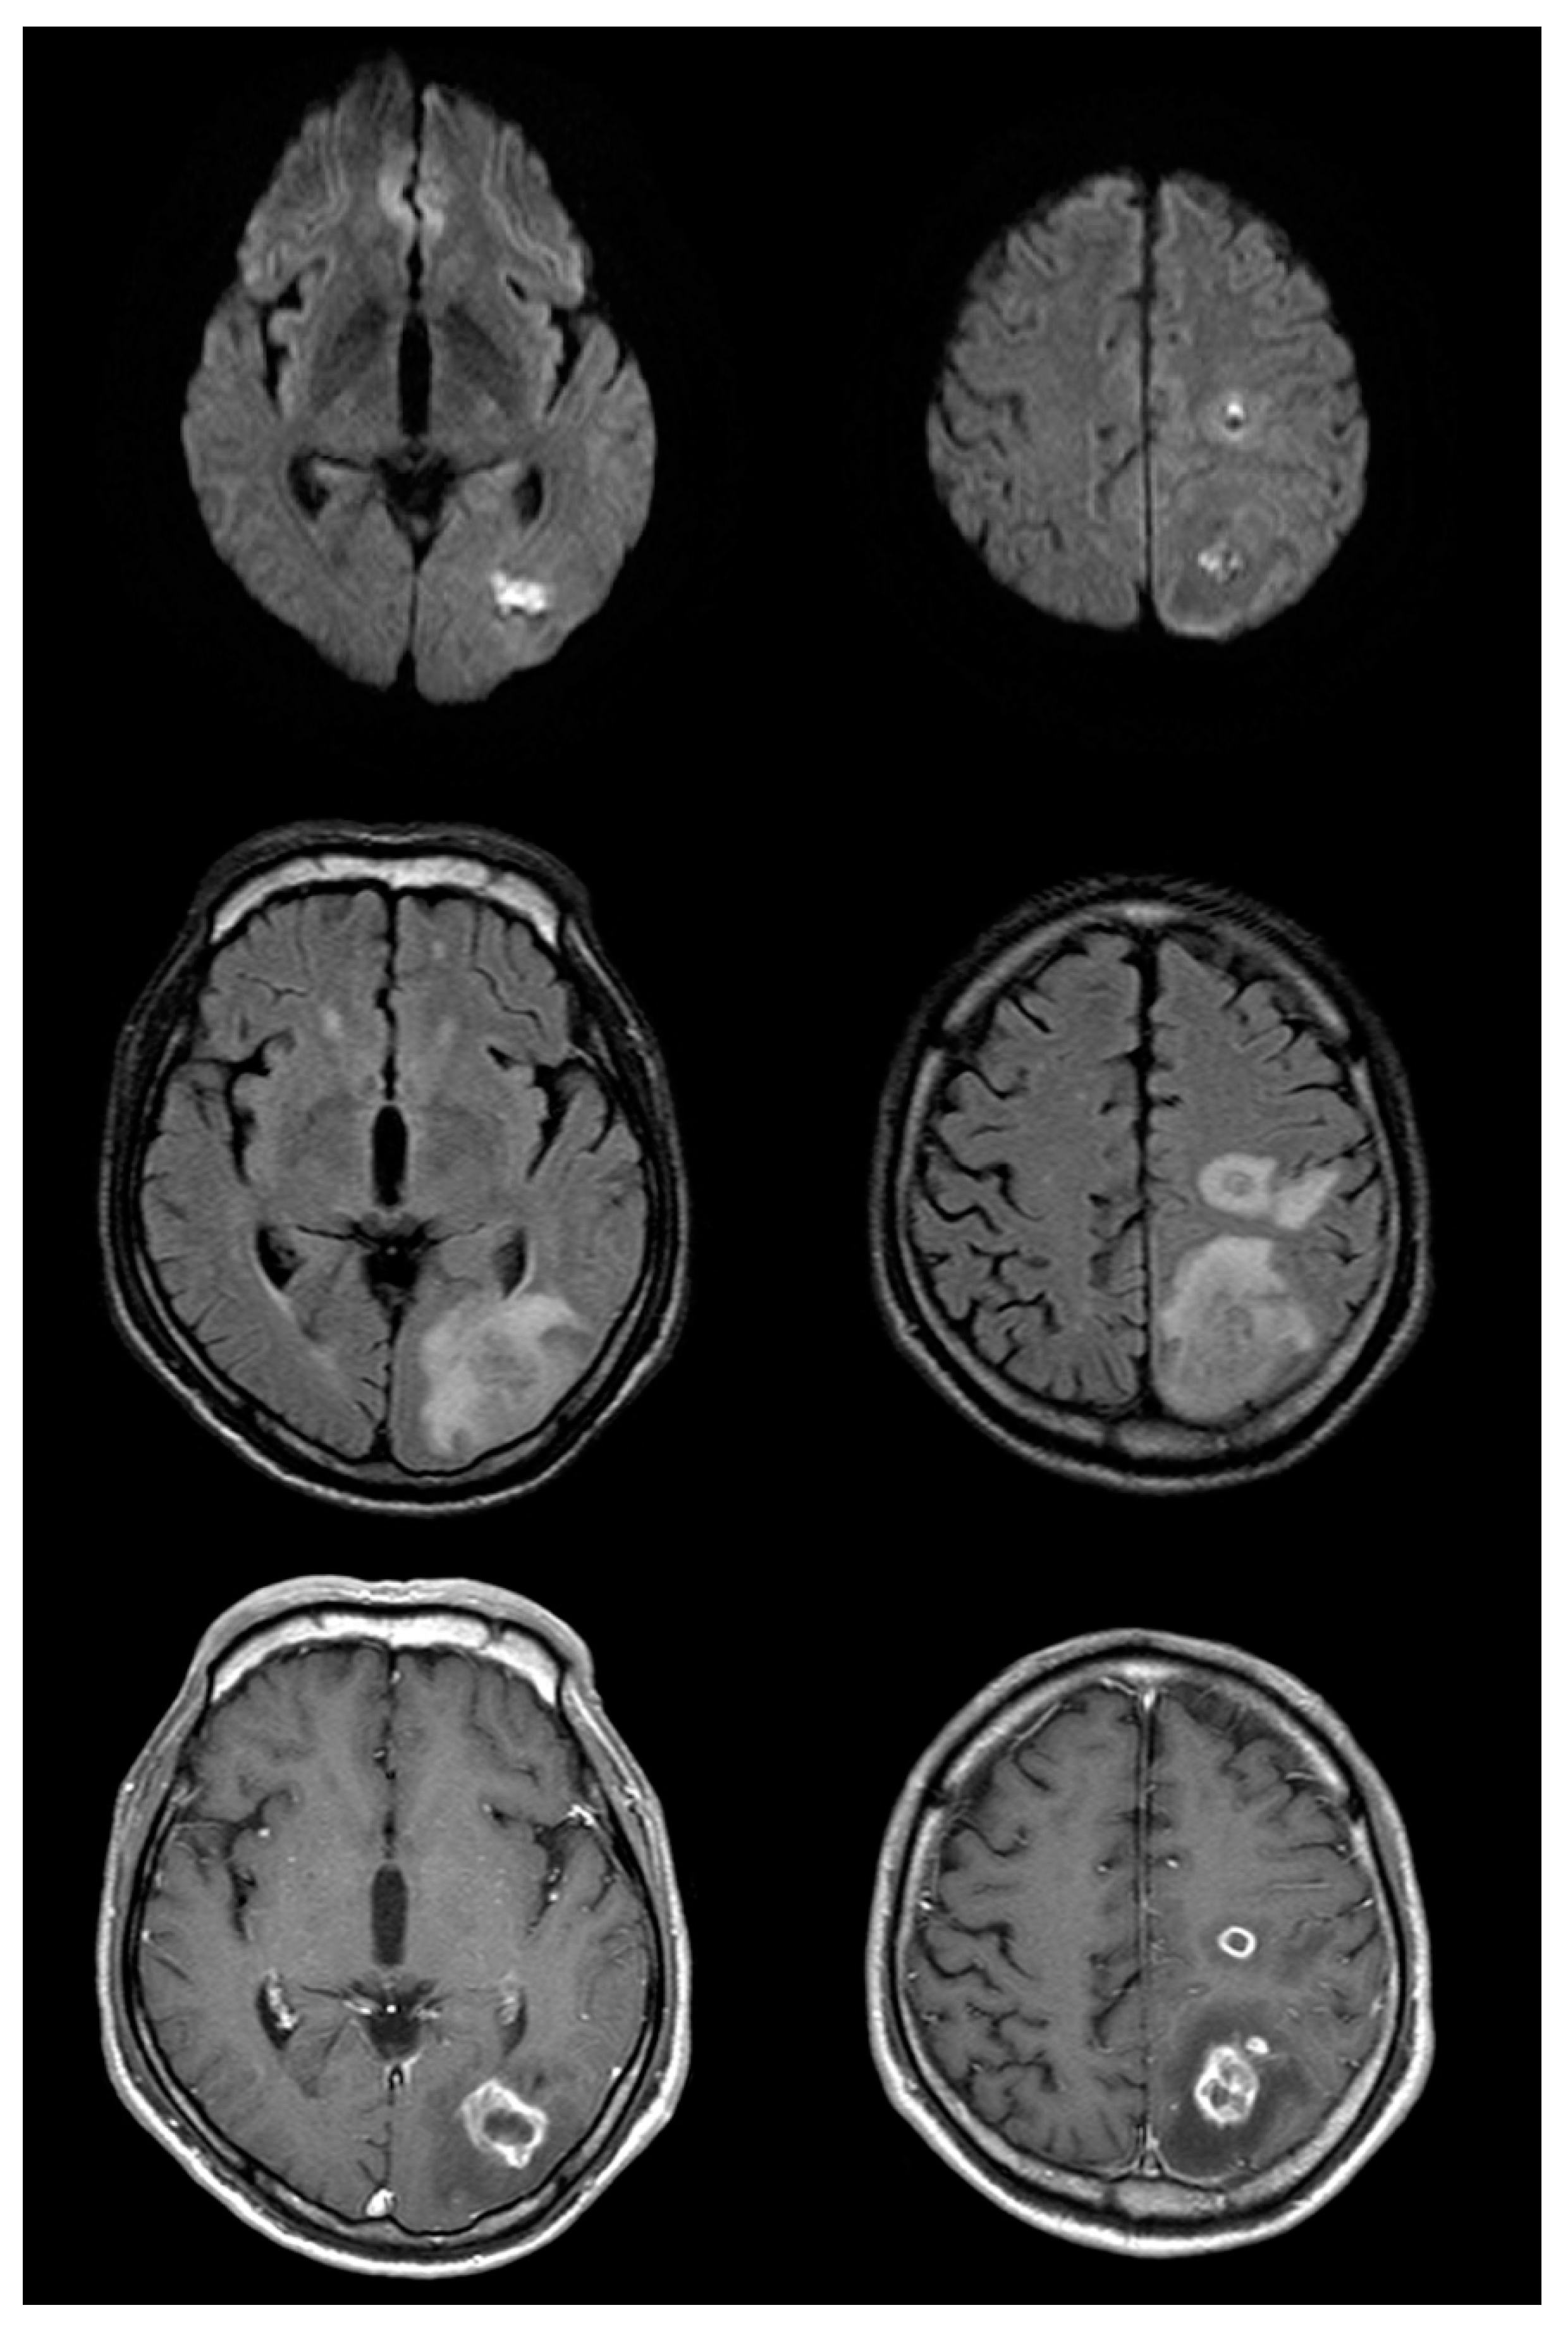

Figure 2.

Follow up brain magnetic resonance imaging on the eleventh day after symptom onset (top row: diffusion-weighted imaging (DWI); middle row: fluid-attenuated inversion recovery (FLAIR); bottom row: post-gadolinium). There is significant interval change with enlargement of the lesions on DWI and FLAIR images, as well as significant vasogenic edema. Post-gadolinium T1-weighted images show somewhat thick and irregular but complete ring enhancement.